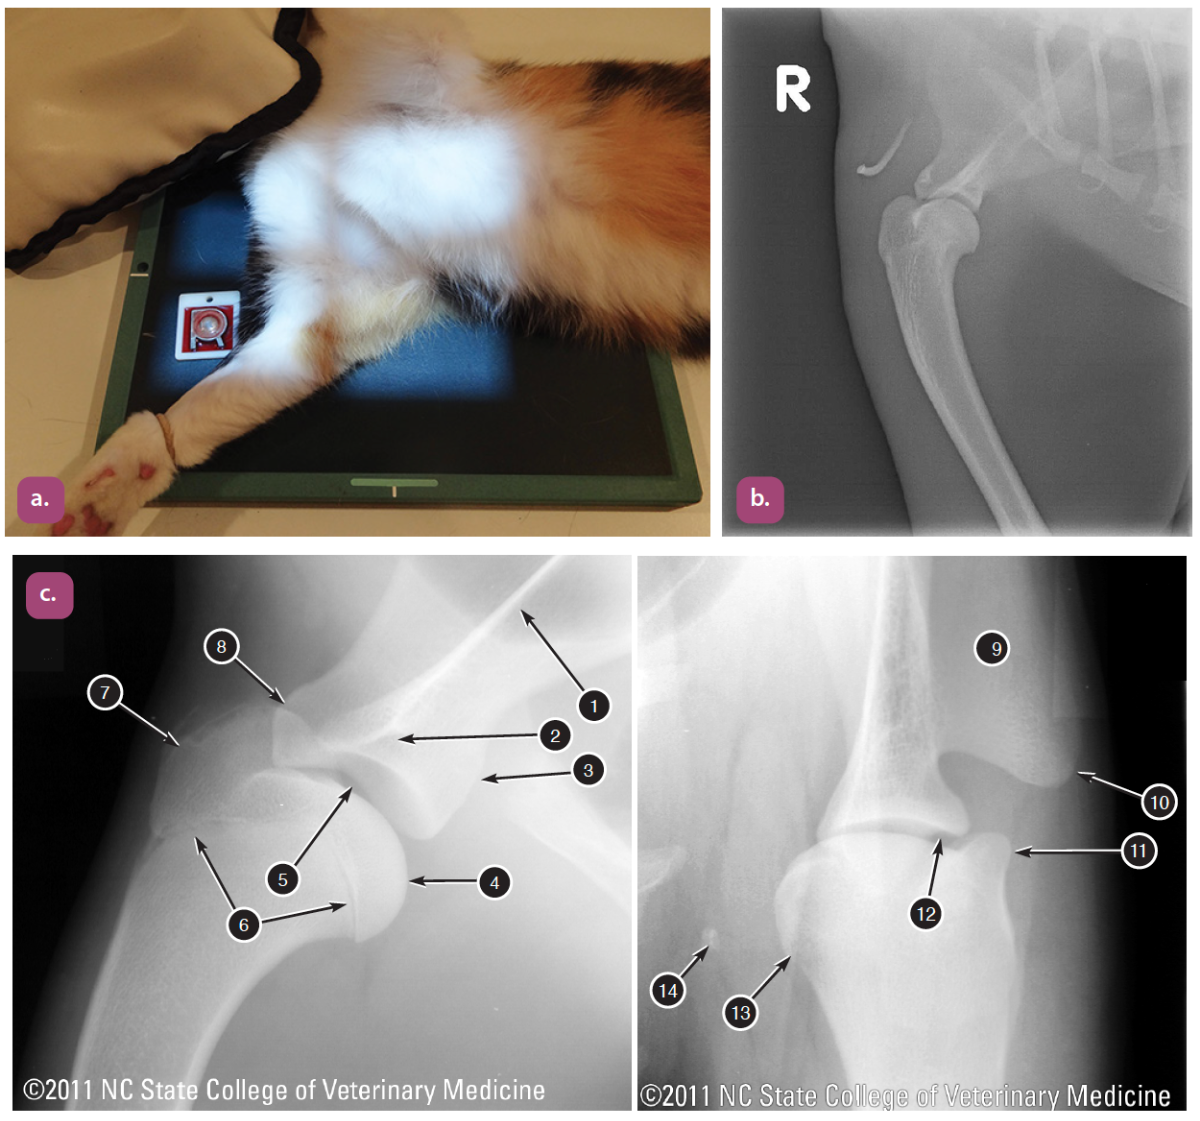

mediolateral projection of the stifle

Caudocranial projection of the stifle